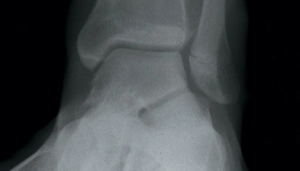

A 15-year-old adolescent Caucasian male with no significant past medical history presented to the clinic with gradually worsening left ankle pain over the past 2 weeks, ever since he started his football practice. He complained of dull aching pain at the lower end of his left leg for the past 4 months, which was slightly relieved by over-the-counter nonsteroidal anti-inflammatory drugs (NSAIDs). He twisted his left ankle and noticed further worsening pain, which prompted this doctor visit.